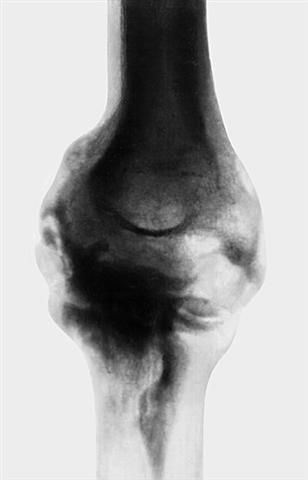

Рис. 13а). Рентгенограмма локтевого сустава при параартикулярной оссификации — переднезадняя проекция.